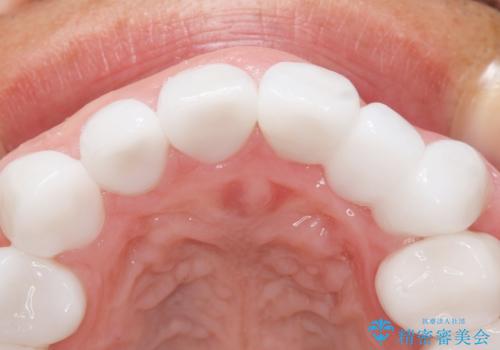

クラウンの色味・形態の修正や患者様のお仕事のご都合で来院できない期間があったことにより、予想より治療期間が長くなってしまいましたが、審美的な仕上がりにご満足頂けました。

矯正治療で歯並びを整えたいというのが歯科医師である私の本心でしたが、患者様の強いご希望によりオールセラミッククラウンによる補綴治療を行いました。

クラウンの色味に関して、自然な白さ(シェードA1~NW0.5)のクラウンを作製・試適したところ「もっと白くしたい」と希望され、当院で最も明度の高い色(シェードNW0)に修正しました。

被せ物の種類:オールセラミッククラウン スタンダード (シェード:NW0)